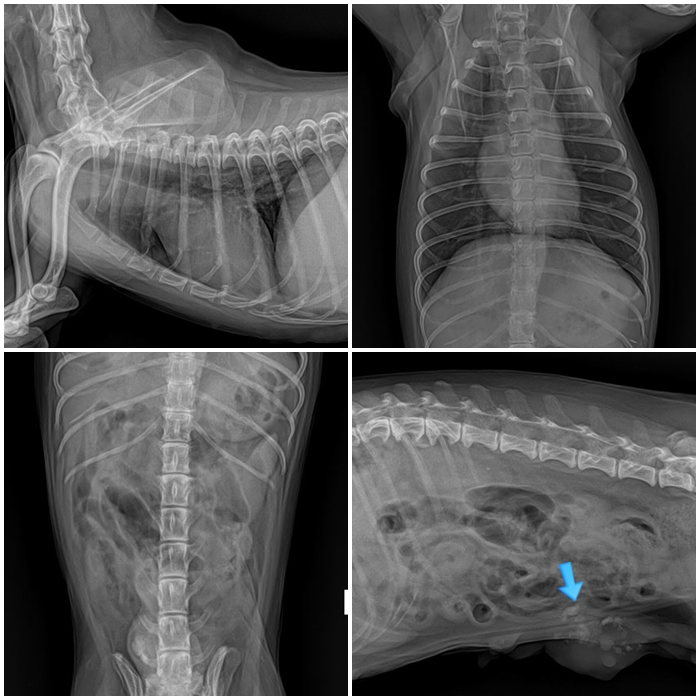

수술 전 방사선 사진 / 출처: 라온동물메디컬센터

흉부 방사선 사진에서는 전이 소견은 없었으며, 유선 종양 부위 일부에서 석회화가 확인되었습니다.